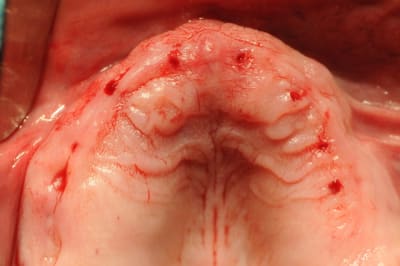

C'est une question que je me pose, car je viens de faire un cas comme ça mercredi matin.

Au départ j'avais plutôt prévu de faire un lambeau d'accès comme d'habitude avec sutures et tout et tout...

Étant donné que j'avais une autoroute en matière de crête osseuse, je me suis dis " et puis zut, restons dans le couloir prothétique et plantons en aveugle".

Une bonne connaissance du scan était nécessaire, et des petits contrôles radios pendant la pose bien évidemment pour connaître la longueur de perçage et savoir quand mon implant allait être juxta-crestal.

petits commentaires:

- J'ai trouvé ça super de ne pas avoir à faire de sutures

- l'un des implants est volontairement incliné car il vient longer le plancher sinusien. Je n'avais pas envie de faire de Summers et le patient ne voulait pas de soulevé de sinus.

Est ce que les cellules gingivales vont réduire mes chances d'ostéointégration ?

Faites vous régulièrement ce type de technique ?

Je ne pense pas qu'on puisse le faire chez tous le monde, mais là, j'avais de la crête, de la gencive attachée et de l'os à profusion...